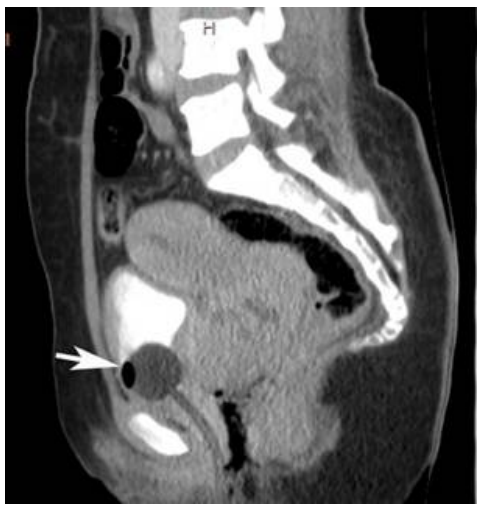

74 一位 30 歲女性,因腹痛接受下腹部電腦斷層檢查呈現異常卵巢如下圖,下列敘述何者最正確?

(A)畸胎瘤 (B)子宮肌瘤 (C)巧克力囊腫 (D)輸卵管卵巢膿瘍